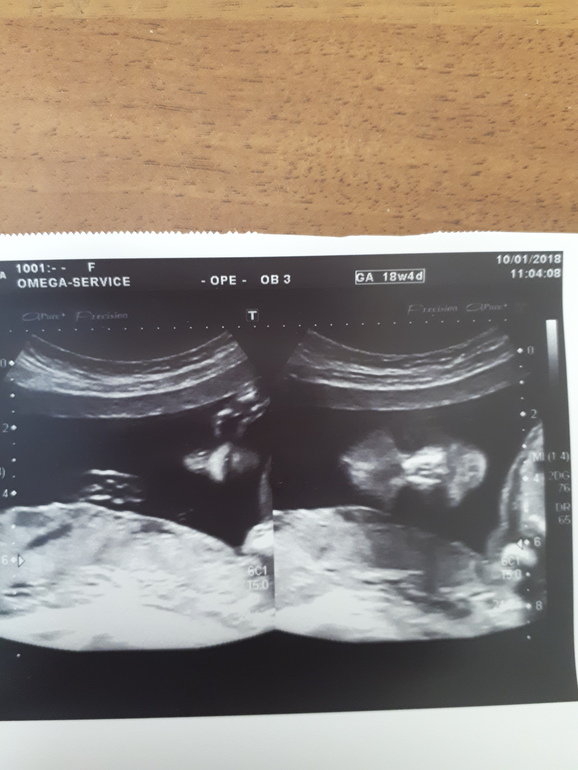

Гляньте кто?)))

Вопросы про УЗИ, обследования и анализы: что, где, как, когда?Сегодня был второй скрининг, 18-19 нед. С малышом всё отлично. С таким нетерпение ждала этого дня, что бы узнать пол, но мне ничего не сказали 😡, второй раз уже врач говорит мне, что пол я узнаю после родов, это типа шутка такая? На мой вопрос, кто в животике живет, ответил что половые органы сформированы в срок. На регистратуре уже дали бумагу с результатами УЗИ и фото для истории (на котором я думала будет полный плод: голова, ручки, ножки и т.д.) а в итоге это я так поняла половые органы, КОГО мне б знать???

Слева нос, справа череп. Не понятно. Если горит сходите платно. Я б разнесла УЗИста.

А я вижу тут, слева трубу и в трубе сперматозоид)))) а справа будто фото таза снизу и половые органы, вот только чьи))

Ручку я тоже заметила, вот нос и губа под сомнениями))) там такой носяра получается))) больше чем у нас с мужем 😃 и губа тоже жесть, почему тогда глаз не видно, а на втором фото если перевернуть его, то да, видно что череп, но с какого ракурса снято, если это с лица, то нос непонятен, губ не видно, я уже ужасы вижу, справа аж глаз увидела хитрый, брр, воображение зашкаливает, надо заканчивать с этим ребусом)))

там подбородок, 2 губы и нос со стороны ноздрей. у меня видео с моего узи есть второй дочей,там такие же ракурсы были. красивый малыш) а узист конечно да..хотя бы профиль сфоткал. на фотках обычно такое не печатают..